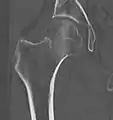

A case demonstrating a possible order of imaging in initially subtle findings:

X-ray showing a suspected compressive subcapital fracture as a radiodense line

CT scan shows the same, atypical for a fracture since the cortex is coherent

T1-weighted, turbo spin echo, MRI confirms a fracture, as the surrounding bone marrow has low signal from edema.